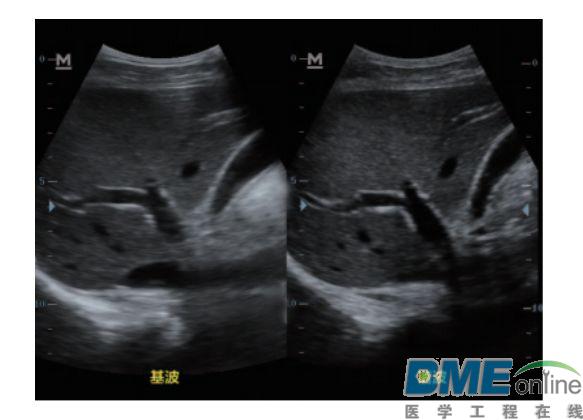

设备型号DP-50 全自动便携式超声诊断系统(迈瑞),该设备为DP 系列超声的较高级版本,具有iTouch 图像一键优化、 iBeam 复合成像、iClear 斑点噪声抑制、宽带频移谐波等技术。

宽带频移谐波技术: